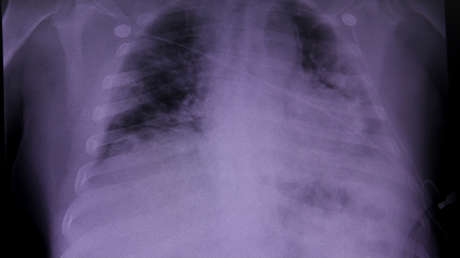

Sánchez empezó a sentirse mal en abril, y aunque pensó que se recuperaría pronto, su salud se deterioró rápidamente. Dado que el covid-19 produjo en el paciente un daño pulmonar severo, tuvo que ser internado en una unidad de cuidados intensivos. Además, permaneció por 116 días conectado a un ventilador mecánico y recibió oxígeno durante tres meses, recogen medios locales.

El médico Rajat Walia, director del programa de trasplantes del hospital, señaló que la operación fue el último recurso. "Hay un punto en el que sabemos que los pulmones no se van a recuperar; tal fue el caso de Arthur".